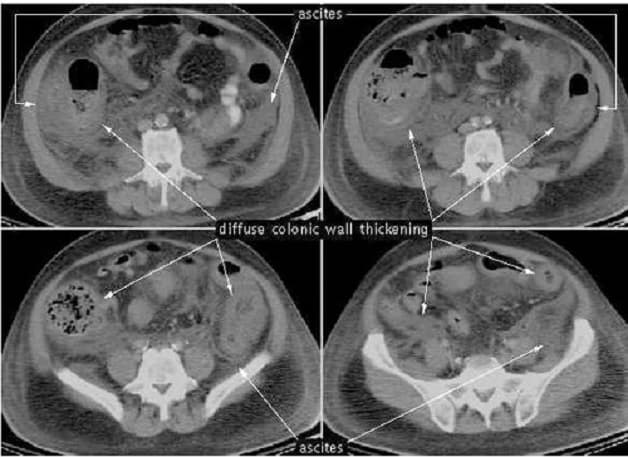

Nếu xuất hiện các triệu chứng nghiêm trọng, bác sĩ có thể tiến hành chụp X-quang hoặc quét CT bụng để tìm các biến chứng. Biến chứng của viêm đại tràng màng giả gồm phình đại tràng hoặc vỡ ruột.